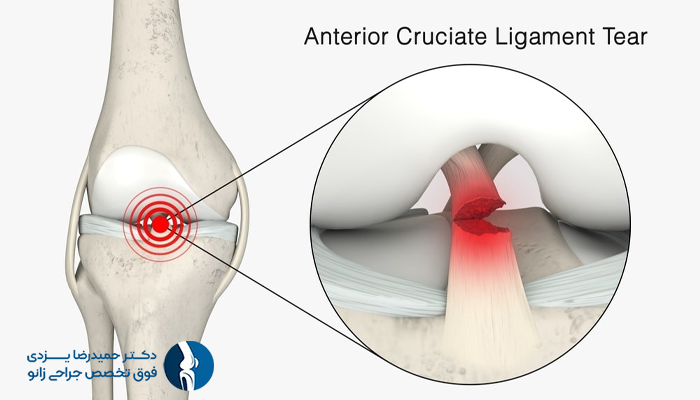

آسیبدیدگی رباط صلیبی قدامی (ACL)

آسیب رباط صلیبی قدامی (ACL) یکی از شایع ترین آسیب های ورزشی زانو در ورزشکاران بوده که در اثر توقفهای ناگهانی، تغییر مسیرهای سریع، یا فرودهای نادرست در ورزشهایی مانند فوتبال، بسکتبال و اسکی دانهیل ایجاد میشود.

این نوع آسیب با علائمی نظیر صدای ترکیدن زانو، درد شدید، تورم فوری و احساس عدم پایداری همراه است. بروز چنین شرایطی ورزشکار را از ادامه فعالیت بازنگه میدارد و در صورت عدم درمان مناسب، مشکلات جدیتری نظیر آرتروز زانو را به دنبال خواهد داشت.

درمان آسیب ACL بسته به شدت آن، از استراحت و تمرینات توانبخشی تا جراحی ACL و بازتوانی متغیر است. البته استفاده از برنامههای تمرینی پیشگیرانه، خطر بروز این آسیب را به میزان قابلتوجهی کاهش میدهد.